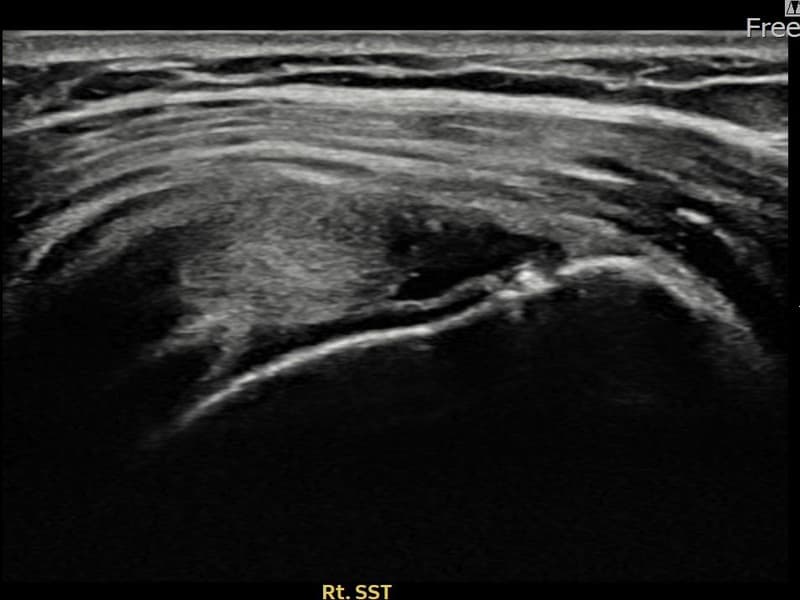

Before

시술 전 초음파 측정 결과 파열 크기는 12mm × 4mm (힘줄 두께의 약 48% 결손)로 확인되었습니다. 시술 전 초음파에서 우측 극상근건 관절면측의 에코 단절과 힘줄 두께 감소가 확인되었습니다. 시술 후 초음파에서 힘줄 연속성이 회복되고 에코 패턴이 균질하게 개선된 것이 관찰되었습니다.

40대 후반 여성 환자분으로, 아이 돌봄과 집안일을 도맡아 하시며 어깨를 반복적으로 사용하다 통증이 생겨 내원하셨습니다. 처음에는 무거운 물건을 들 때만 아팠으나 점차 팔을 수평으로 올리는 것 자체가 어려워진 상태였습니다. 초음파 검사에서 우측 극상근건 관절면측 부분파열이 확인되었으며, 비수술 축소봉합술로 치료 계획을 수립하였습니다. 시술 당일 귀가하셨고 보조기 착용 4주, 이후 단계적 재활을 진행하였습니다. 시술 14주 후 추적 초음파에서 힘줄 연속성이 완전히 회복된 것이 확인되어 통증 없이 일상 복귀에 성공하셨습니다.